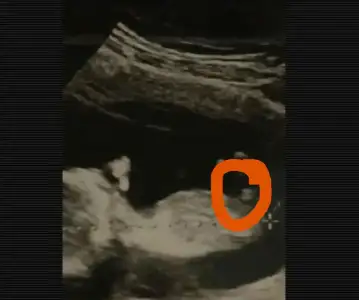

Bnada bı bkınnn kızlarrrr ya

IMG_20190109_171336.webp

Bu gördüğüm nubsa tabi

Hayırlı olsun canım sanki kiz gibi duruyor bana gore

Bide bu nasil bi ultrason ya ozel hastane demi

Bnde anlmdm cnm ya oglmda gttgm hastme ultrasonunuda ck bgnydm gttgm en ıyı ultrasn dye gttım acıkcası farklı doktra bı oncekınıkı gzeldı ultrason bununkı gzel degldı kordonu ckıntı sanms olablrmı kndı ılk kesın kız dedı cıkıntı yok bacaklarnı toplms dedı snra bktı bıdaha bknca ckıntı var kızda dyemm erkkte kordonda olablr dedı

Yani kordon bazwn yanilta biliyo drlari